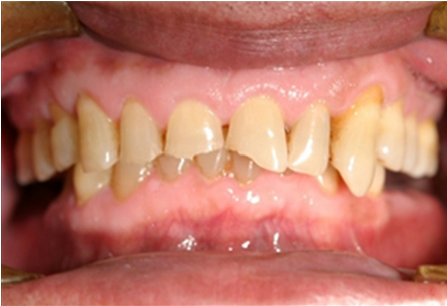

입안으로의 산 역류는 특히 치아 안쪽 표면의 에나멜질을 손상시킬 수 있다. 구강 건조, 입안의 산성 또는 작열감, 구취 및 입천장의 발적이 발생할 수 있다.[27] 위식도 역류병의 덜 흔한 증상으로는 연하 곤란, 물 넘어감, 만성 기침, 쉰 목소리, 메스꺼움 및 구토가 있다.[26]

에나멜질 부식의 징후는 페리키마가 없는 매끄럽고 비단결같이 광택이 나며 때로는 둔탁한 에나멜 표면이 잇몸 경계를 따라 온전한 에나멜과 함께 나타나는 것이다.[28] 수복물이 있는 사람의 경우, 치아 구조가 일반적으로 수복 재료보다 훨씬 빠르게 용해되어 주변 치아 구조보다 "위로 솟아" 보이는 것처럼 보이게 된다.[29]